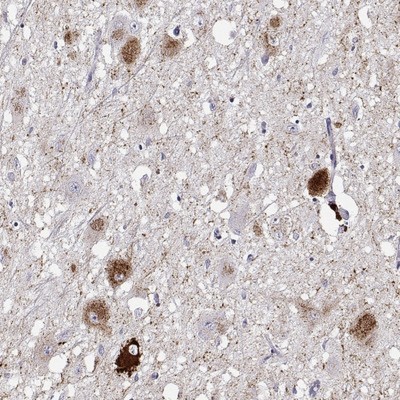

- Immunohistochemistry-Paraffin: VGF Antibody [NBP2-31596] - Staining of human cerebral cortex shows high expression.